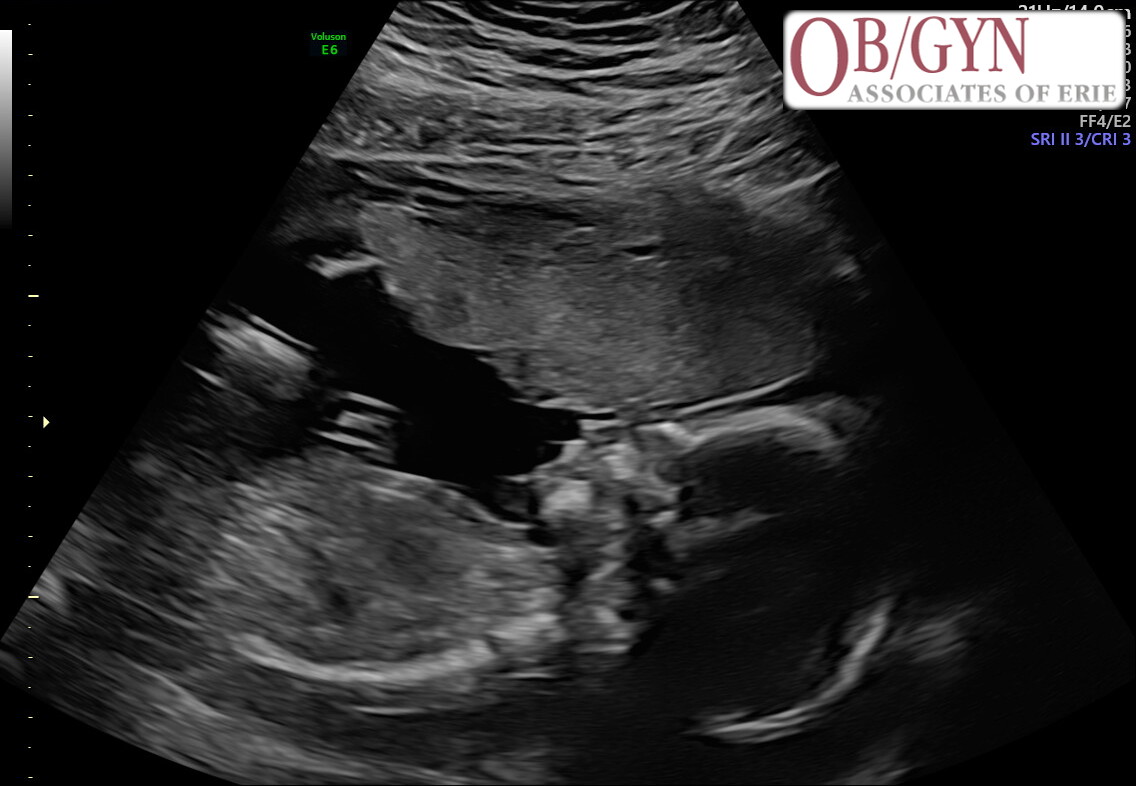

Awaiting the arrival of

Baby LaVette